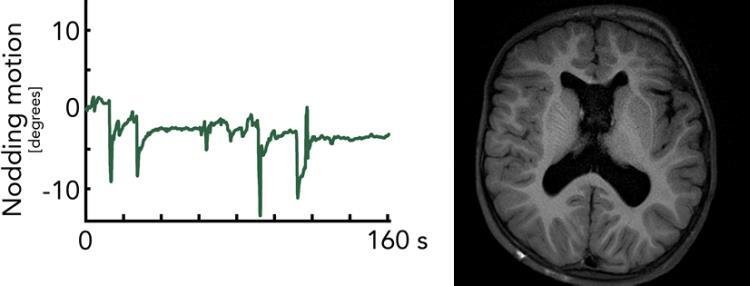

Rörelseövervakning av en av våra barnpatienter som undersökts med vårt rörelserobusta realtidskorrigerade MR-protokoll bestående enbart av egenutvecklade pulssekvenser. Ovan ses barnets ansikte genom point-cloud-kameran. Nedan ses rörelseinformationen (för hela MR-undersökningen), som kontinuerligt används för att flytta MR-bildplanen så att de följer med huvudrörelserna.

Trots rörelsekorrektion i realtid med Tracoline eller WRAD är det fundamentalt svårt att få bra bildkvalitet med 3D-sekvenser med lång TE som för SWI. Även med en ideal rörelsekorrektion leder de fasförändringar i hjärnan (som uppstår vill långa ekotider) till bildstörningar (överst-höger, 3D EPI). Med vår snapshot 2D SWI EPI erhålls ett komplett bildplan på 0.1 s under samma fasbetingelser i hjärnan. Med flera repetitioner av samma bildplan som medelvärdesbildas efter rörelsekorrektion ökas SNR till lämplig nivå.